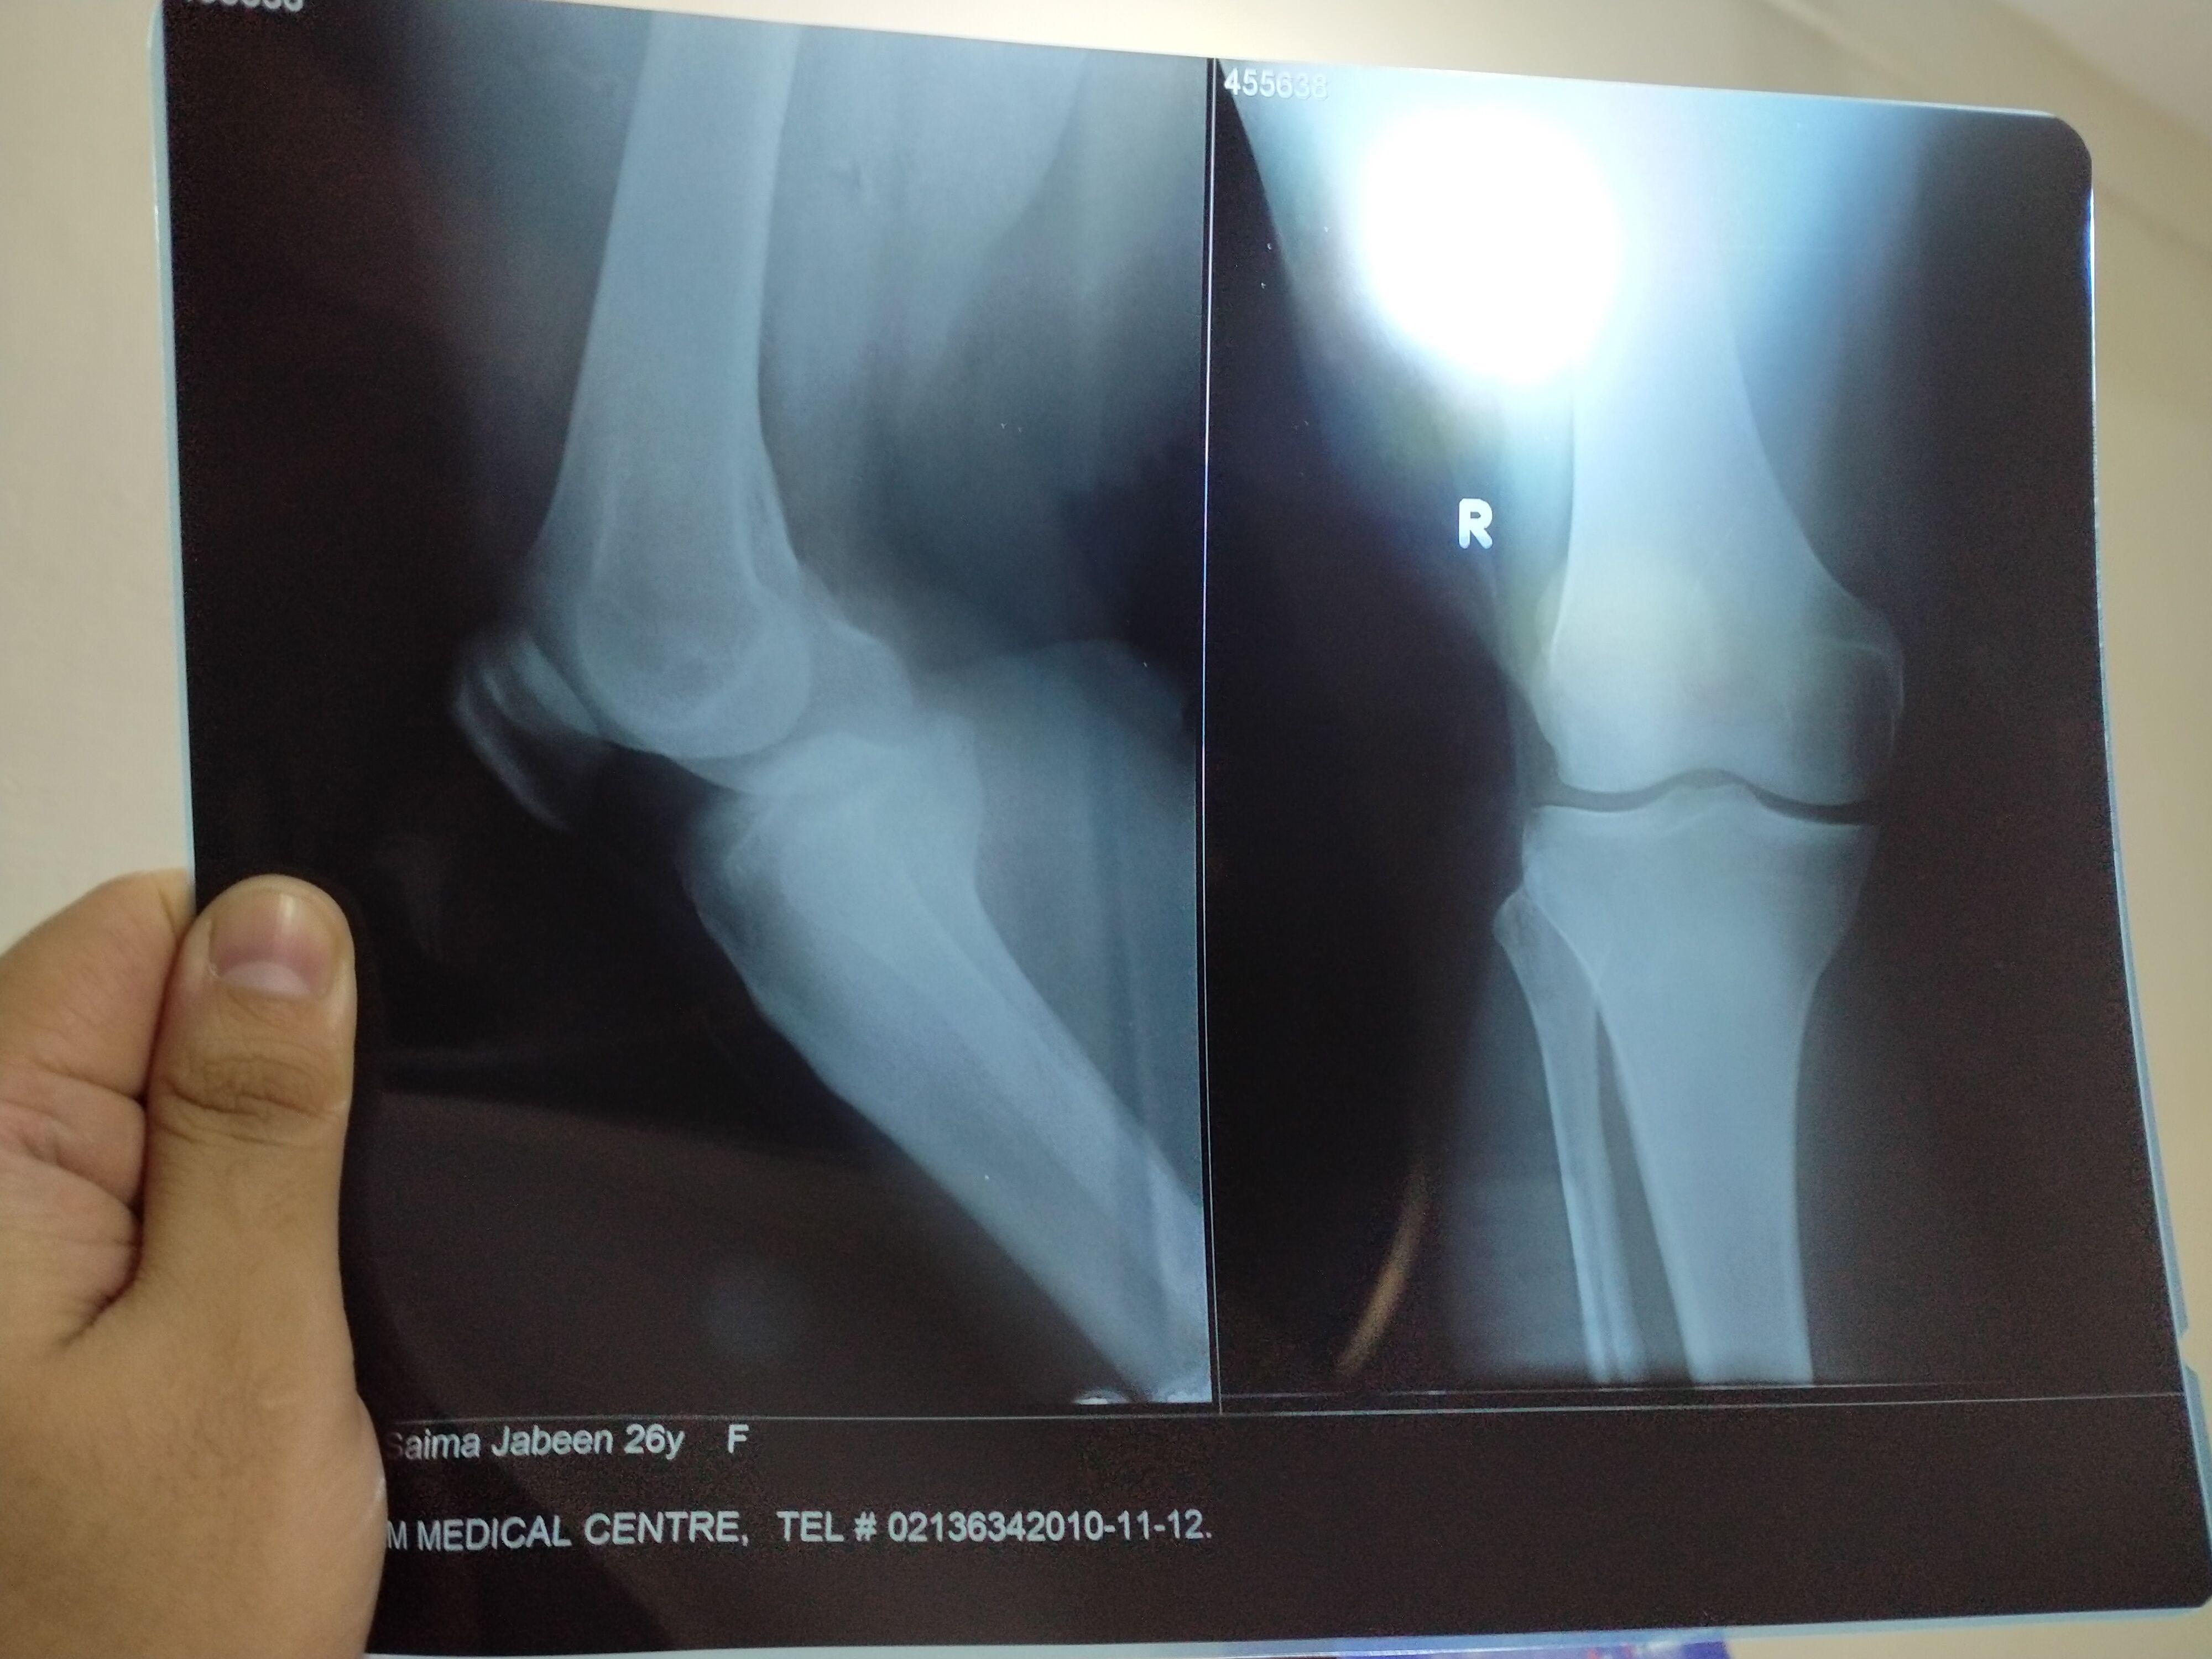

Assalamu alaikum. Mujy knee pain hua tha dr ny x-ray krwaya tw unhony btaya k haddian kamzor hain dodh b pinay ka kaha,gebon tablet use ki thi meiny phr covid hogya us k bd se meiny koi tablet nae li except pain jb band krti hn knee tw uper thigh mein b pain hota hai jo joint haina uper tw thora guide b kardain ab kia weight 96 hai aur height 5.6'

Apny X-Rays ki Pic send kijye.. and please tell if there is any inflammation 042-32591427, 00 Dr.Nabeel Zahid PT

yes you can walk. but pehly ap aik bar assessment krwa lein ta k knee ki condition ka idea ho jay. jahan bhi chek krwaen xrays sath ly k jaen.

you can visit or book online consultation so i can assess you and see your xray to design a treatment for you. It can be due to muscular issue or as well as joint issues.